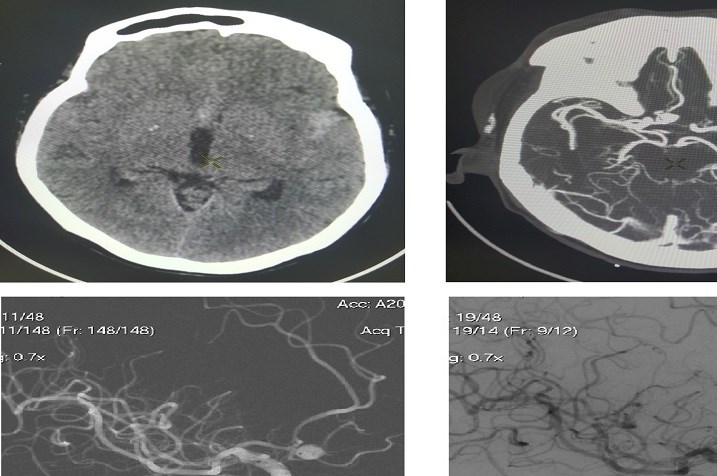

Trong xã hội hiện đại, Đột Quỵ Não không còn là một căn bệnh hiếm gặp, đặc biệt trong bối cảnh hiện nay, khi mà di chứng hậu covid khiến cho cơ...